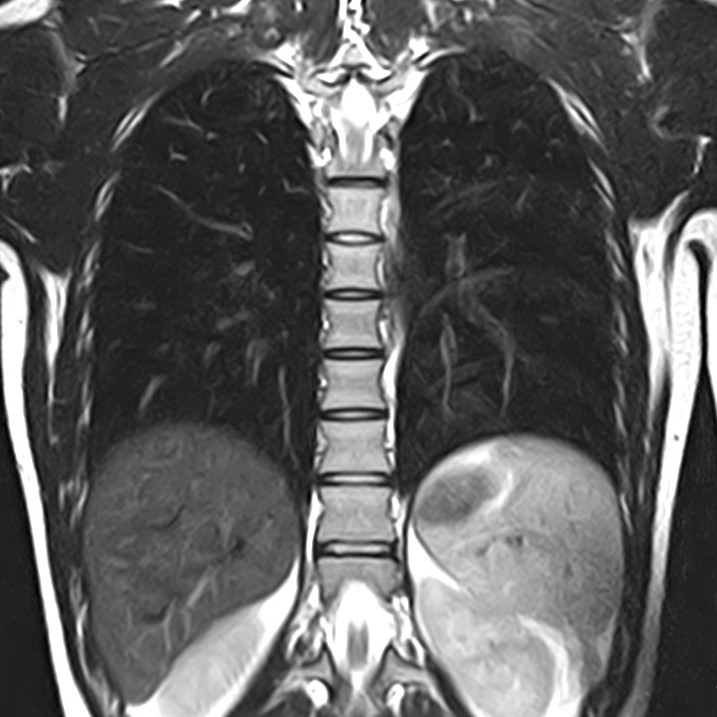

МРТ

Данный метод из всего списка является самым инновационным и современным. Благодаря своему принципу работы, МРТ дает четкую визуализацию с высоким разрешением. Такое исследование, в рамках органов грудной клетки, используется для исследования органов средостения. К сожалению, такое исследование не подходит для визуализации мельчайших очагов поражения в легочной ткани. Но стоит отметить, что существенным плюсом является отсутствие лучевой нагрузки, а вот существенным минусом со стороны пациента являются дороговизна исследования, длительность проведения исследования, а также наличие ряда относительных и абсолютных противопоказаний.